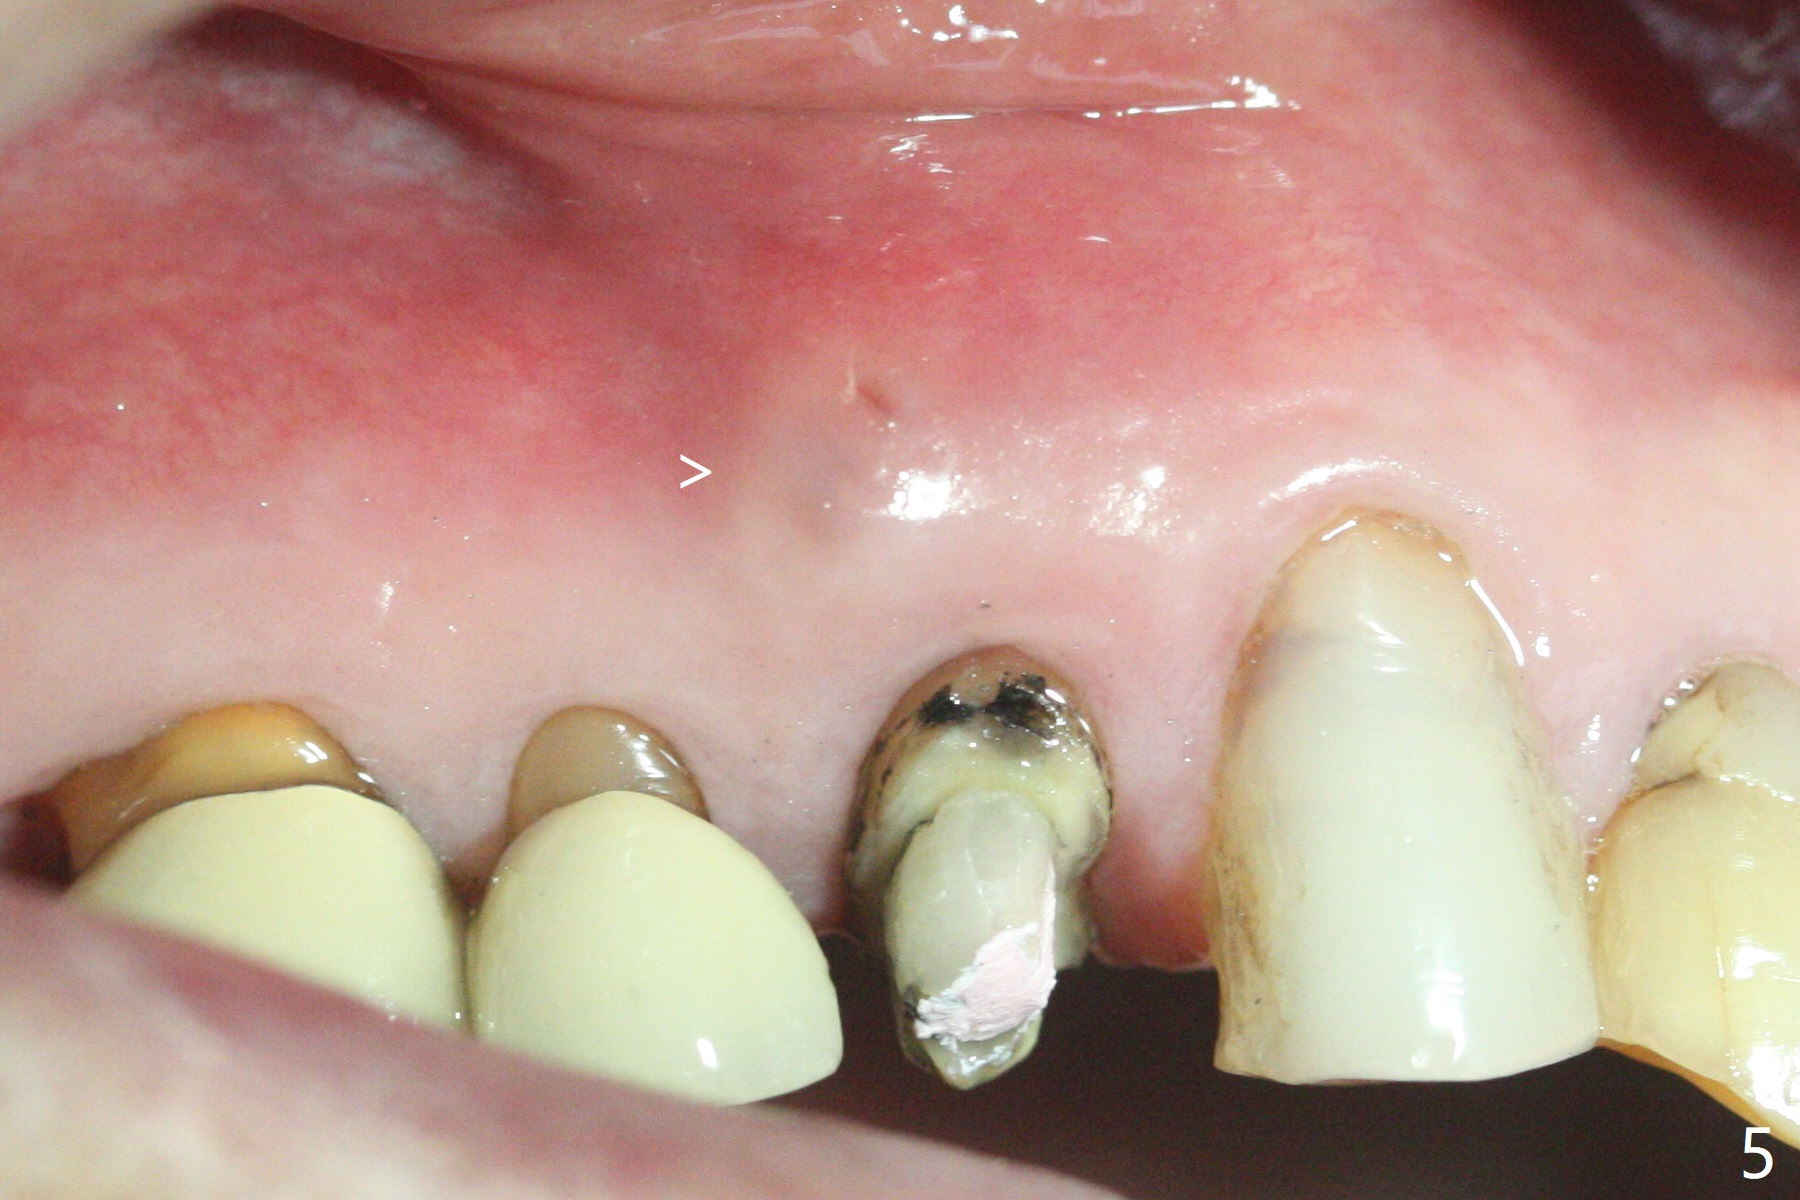

A 90-year-old man (bruxer) has porcelain fracture at #4. PA happens to reveal large PARL at #5 (Fig.1). CT taken a year ago shows missing buccal canal (Fig.2). Bone loss seems to be extensive (Fig.3,4 (root fracture?)). Access to the canal through PFM fails; the crown has to be removed (Fig.5). Fortunately the buccal canal is found and negotiable.